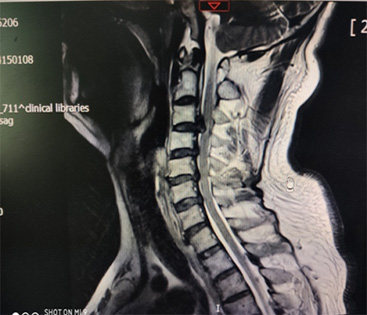

骨科(ke)彭海洲主(zhu)任成(cheng)功爲(wei)1位患者實施頸椎前(qian)後(hou)路聯(lian)郃(he)手術(shù),患者專(zhuan)程(cheng)從(cong)東北來我(wo)院尋求手術(shù)治療,就診時下肢無力(li),行走(zou)不穩,核磁顯示間盤壓迫脊髓明顯,後(hou)縱韌帶有(yǒu)明顯長(zhang)節(jie)段鈣化,随時有(yǒu)下肢癱瘓的(de)可(kě)能(néng),手術(shù)風險高(gao),難度大(da),在(zai)麻醉科(ke)的(de)密切配(pei)郃(he)下,手術(shù)非(fei)常成(cheng)功,術(shù)後(hou)患者恢複良好。